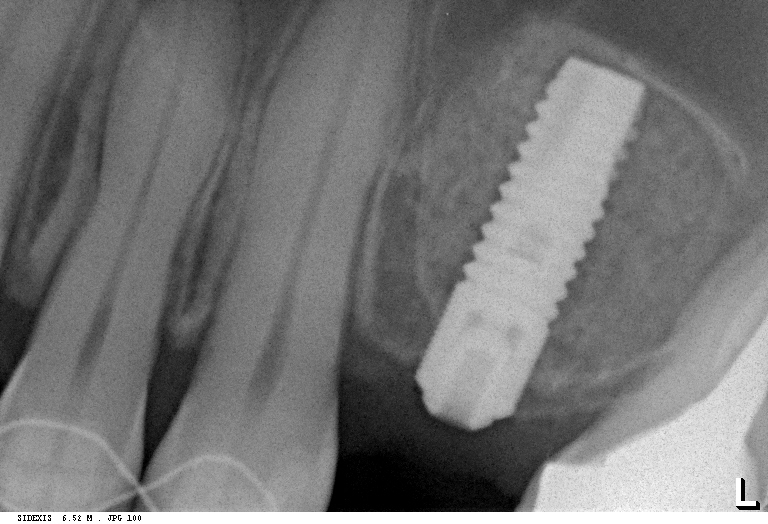

— если площадь операционной раны больше 2 кв. см. Акцент при этом делается на травматичность операции (чем меньше, тем лучше). Если при имплантации мы можем свести площадь операционной раны к минимуму:

то при остеопластике такое удается нечасто, ведь в большинстве случаев остеопластика требует донорского участка для забора аутокостной стружки или костных фрагментов. Наверное, единственное исключение, когда критерий размера раны работает — это расщепление альвеолярного гребня: